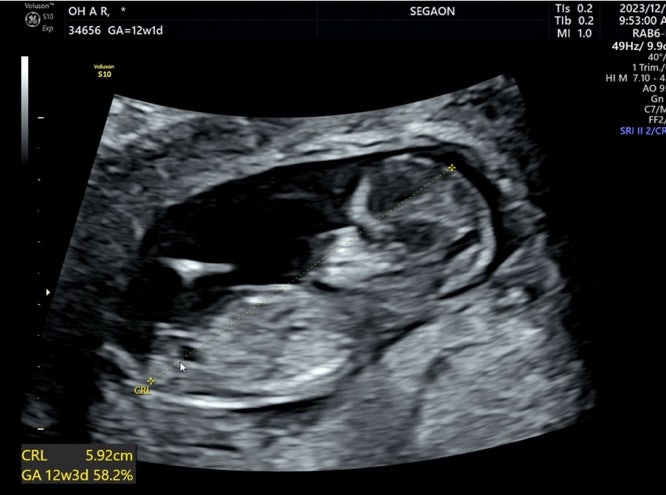

임신 12주 / 1차 기형아검사 / 심장소리반전? / 초음파성별

12주 1일차에 1차 기형아검사 받고 왔어요! 초음파 선생님께서 6분정도 자세히 봐주셨고 남편도 함께 들어...